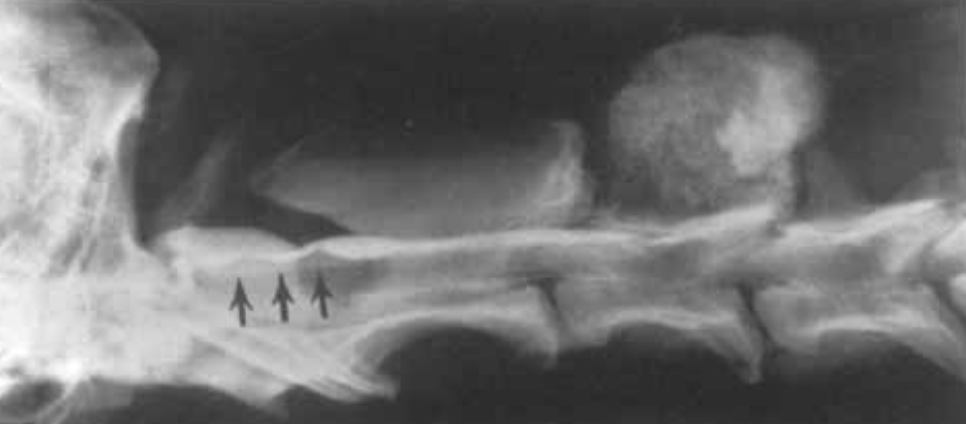

What type of IVDD lesion is conventional CT most capable of identifying?

Mineralized Hansen type 1 discs in chondrodystrophic breeds

Hansen type 2 were rarely mineralized

In what cases is CT myelography often necessary for diagnosis of acute canine myelopathy?